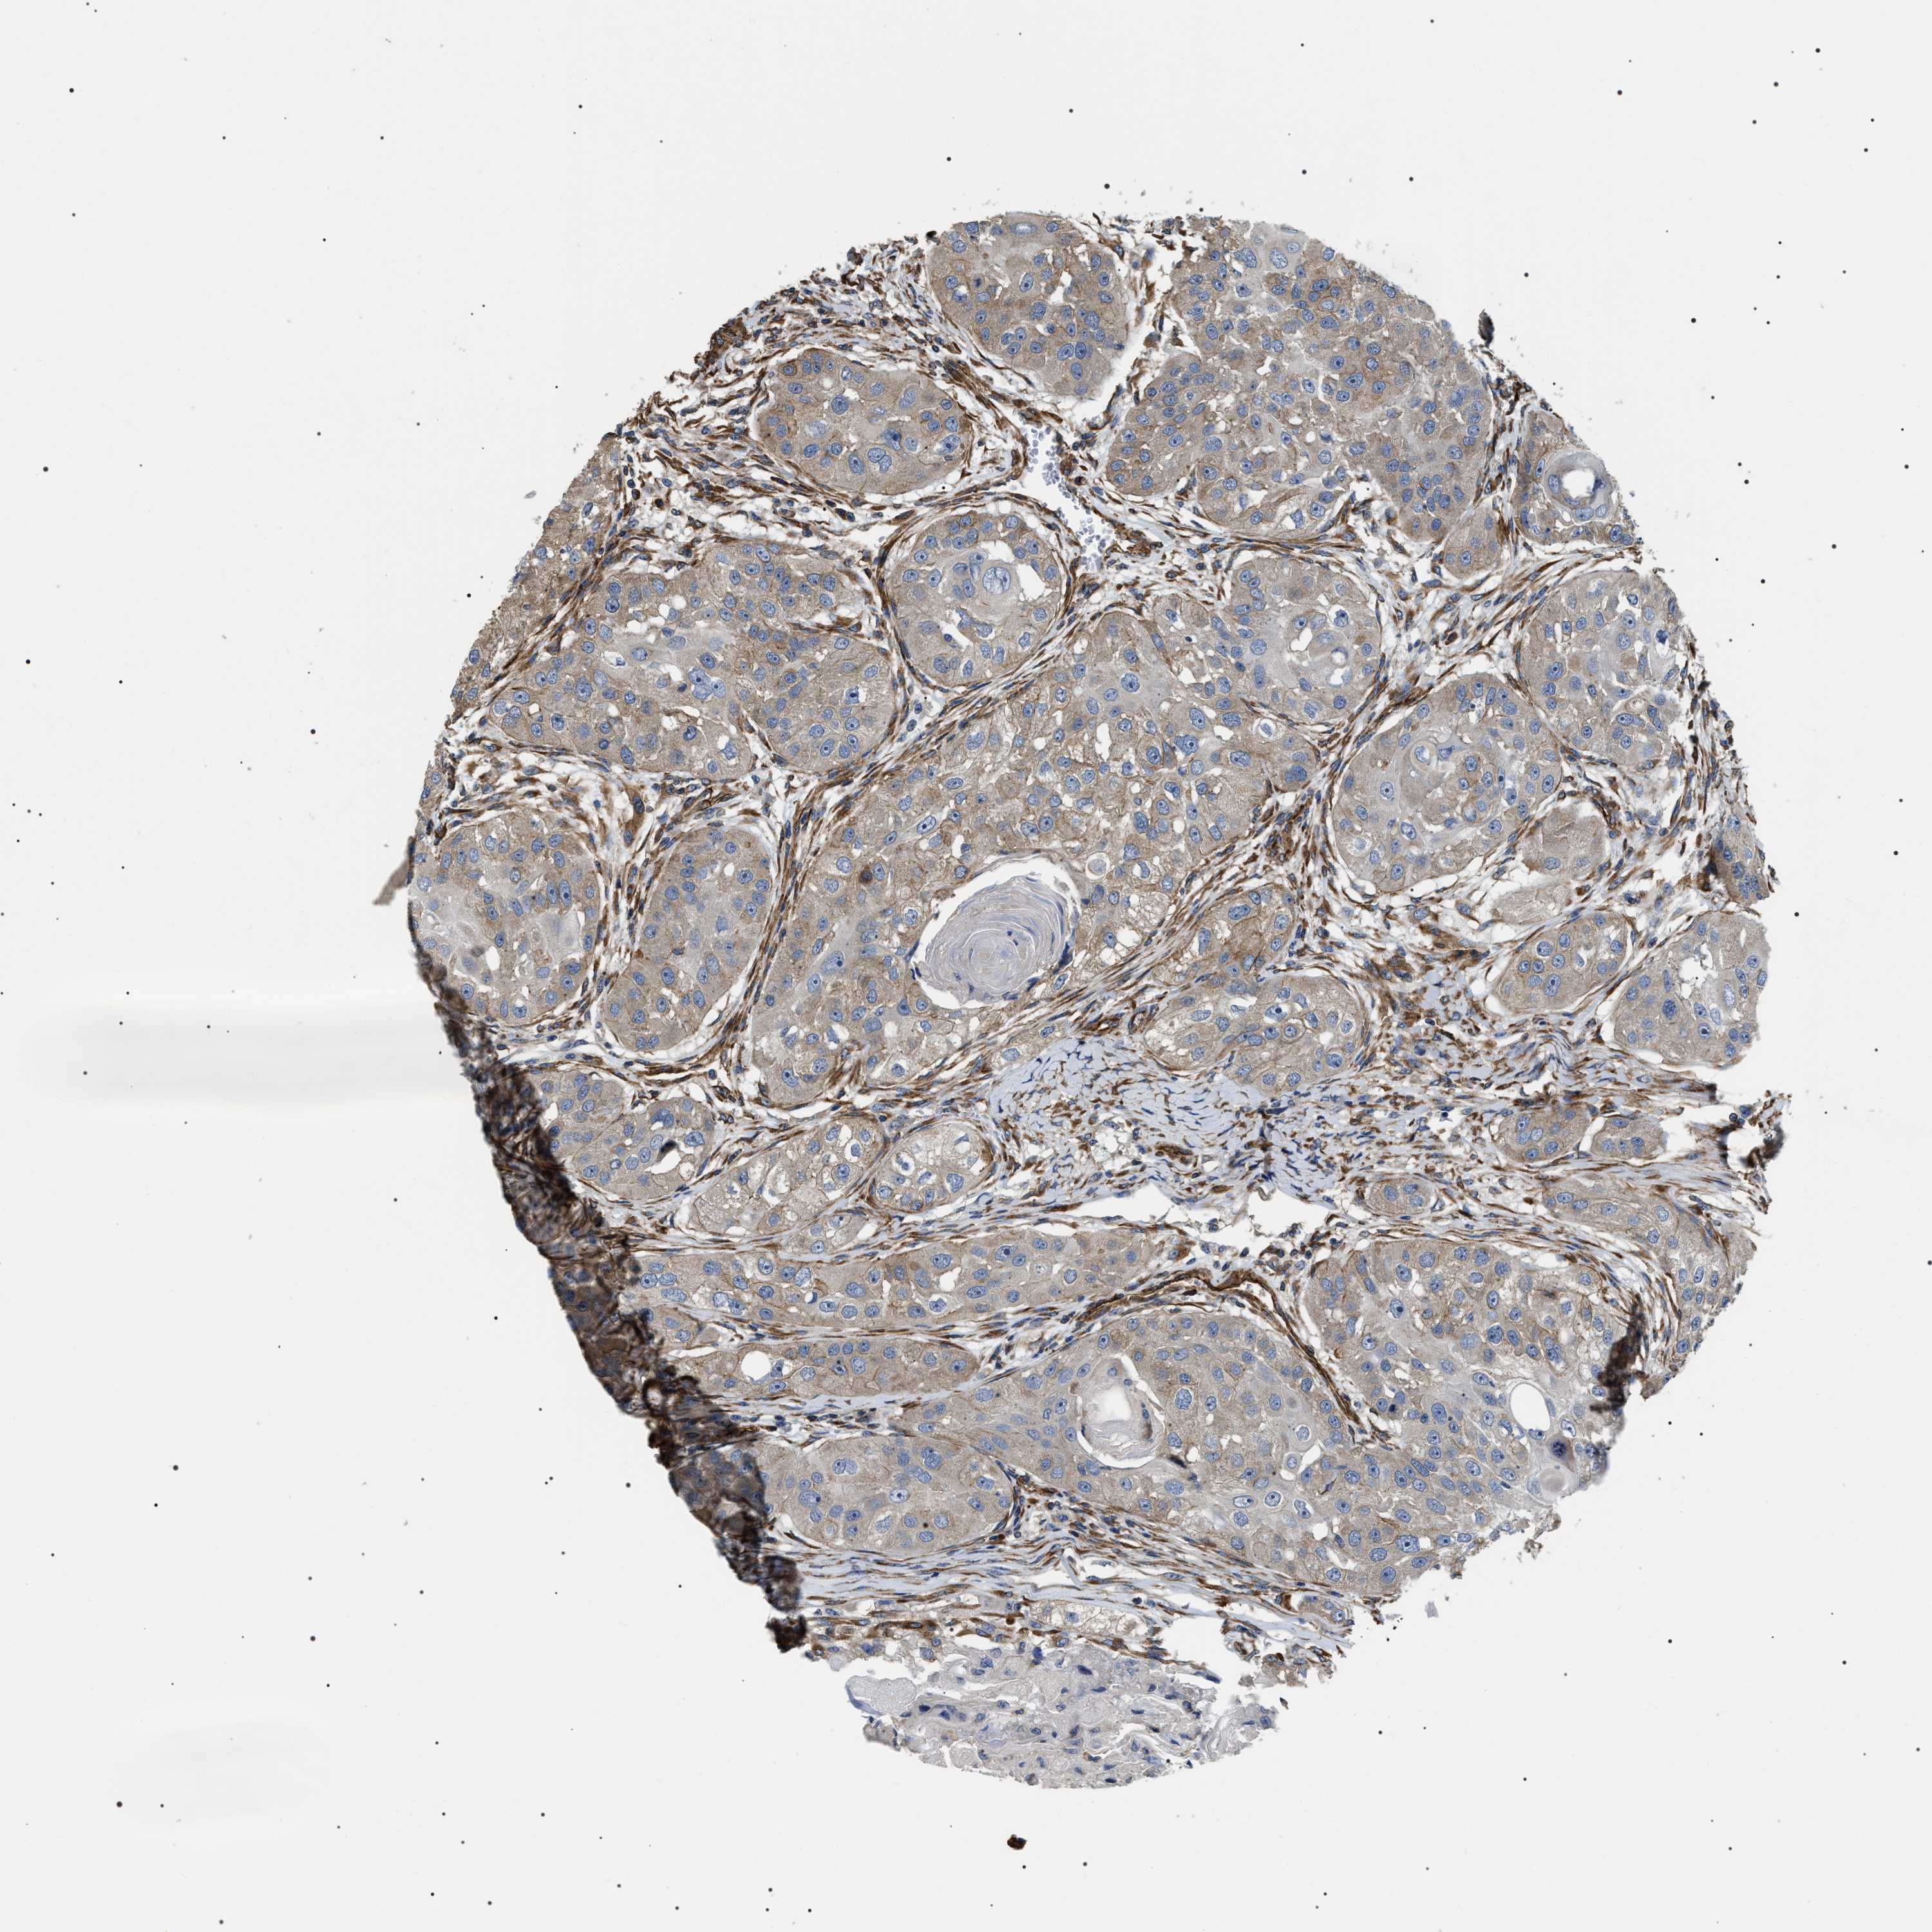

HEAD AND NECK CANCER - Protein expressioni

A mouse-over function shows sample information and annotation data. Click on an image to view it in a full screen mode. Samples can be filtered based on level of antibody staining by selecting one or several of the following categories: high, medium, low and not detected. The assay and annotation is described here.

Antibody stainingi

Antibody staining in the annotated cell types in the current human tissue is reported as not detected, low, medium, or high, based on conventional immunohistochemistry profiling in selected tissues. This score is based on the combination of the staining intensity and fraction of stained cells.

Each image is clickable and will lead to virtual microscopy that enables deeper exploration of all samples and also displays staining intensity scores, fraction scores and subcellular localization as well as patient and tissue information for each sample.

Antibody HPA020386

Squamous cell carcinoma, NOS

Squamous cell carcinoma, metastatic, NOS

Adenocarcinoma, NOS